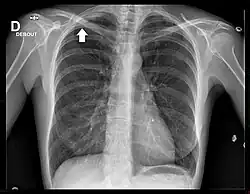

Radiographie thoracique

La radiographie thoracique est un examen de dépistage aisément accessible. Cependant, les tumeurs de l'apex de petite taille sont difficiles à visualiser en raison des superpositions osseuses de la clavicule et de la première côte[18].

Le cliché thoracique de face retrouve le plus souvent un simple épaississement de l'apex thoracique, ou bien une authentique masse pulmonaire englobant l'apex[20]. Une ostéolyse des côtes et du rachis est parfois visible[20].